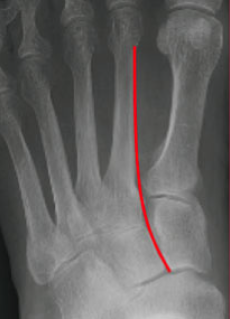

Figure 5: Normal three-column anatomy of Lisfranc complex. A(LEFT) shows the AP view. B(ABOVE) shows the oblique view. C(BELOW) shows the lateral view.